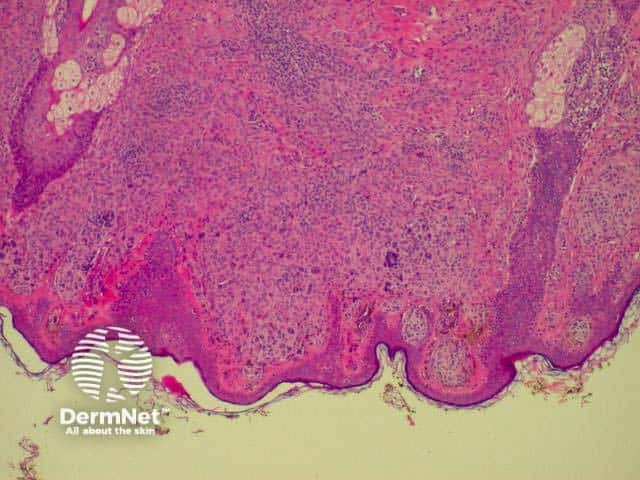

SCC is characterised by proliferation of irregular nests of abnormal squamous cells arising from the epidermis and invading the dermis. Tumours are traditionally divided into well, moderately or poorly differentiated tumours by a subjective assessment of how significantly the tumour cells differ from normal keratinocytes. In general, the greater the degree of keratinization, the better differentiated the tumour is thought to be. Except in the case of very poorly differentiated tumours, this does not have a great bearing on prognosis. More important is the depth and irregularity of invasion, particularly the presence of perineural infiltration, which is associated with a much higher rate of recurrence if not widely excised. The site of the lesion is also important; tumours of the lips and ears have a considerably higher rate of metastasis to lymph nodes.

From the above comments it can be seen that the histological features of SCCs can vary, but in general are:

Pathology of SCC Pathology of SCC Pathology of SCC Pathology of SCC